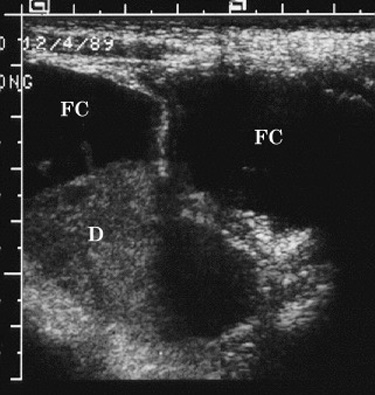

Figure 1. Longitudinal pelvic sonogram

through the right lower quadrant shows a

multiloculated fluid collection (FC). One of the

loculations contains debris (D) of low-level

echogenicity. |